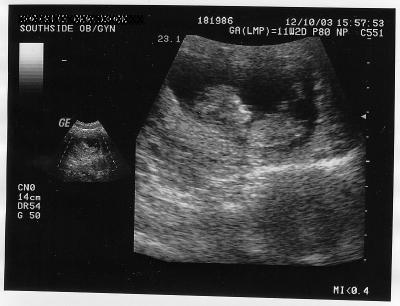

Bebeğin kalp atışlarının artık “ Doppler “ adı verilen cihazla kolayca duyulabildiği hamileliğin 11. haftası itibari ile kalp atışları son derece hızlı atmakta ve dakikada 120 – 140 atış arasında olmaktadır. Aslında bebeğin kalbi çok uzun zamandır hızla atmaktaydı, ancak cihazla duyulabilecek seviyeye ancak erişebilmiştir. Gebeliğin 11. haftası, mide bulantısı, kusma ve halsizlik ile mücadele etmeye çalışan anne adayları için bebeklerinin kalp atışlarını ilk kez duyabilecekleri son derece keyifli ve moral veren bir hafta olmaktadır genelde. Tabii ki kalp atışlarının sesi duyulurken kalp aynı zamanda dört bölmeden oluşan düzgün bir organ haline geldi. Kalp atışlarını duymak ve rutin kontrollerin yapılması için hekim bebeği ultrason ile incelerken, gereken ölçümleri de yaparak gelişiminin yeterli olup olmadığını tespit edecektir. Gebelik 11. hafta görüntüsü ile bebeğin başının tepesinden kuyruk sokumuna kadar olan kısmı (baş-pop mesafesi / CRL) yaklaşık 5 cm civarında olmaktadır.